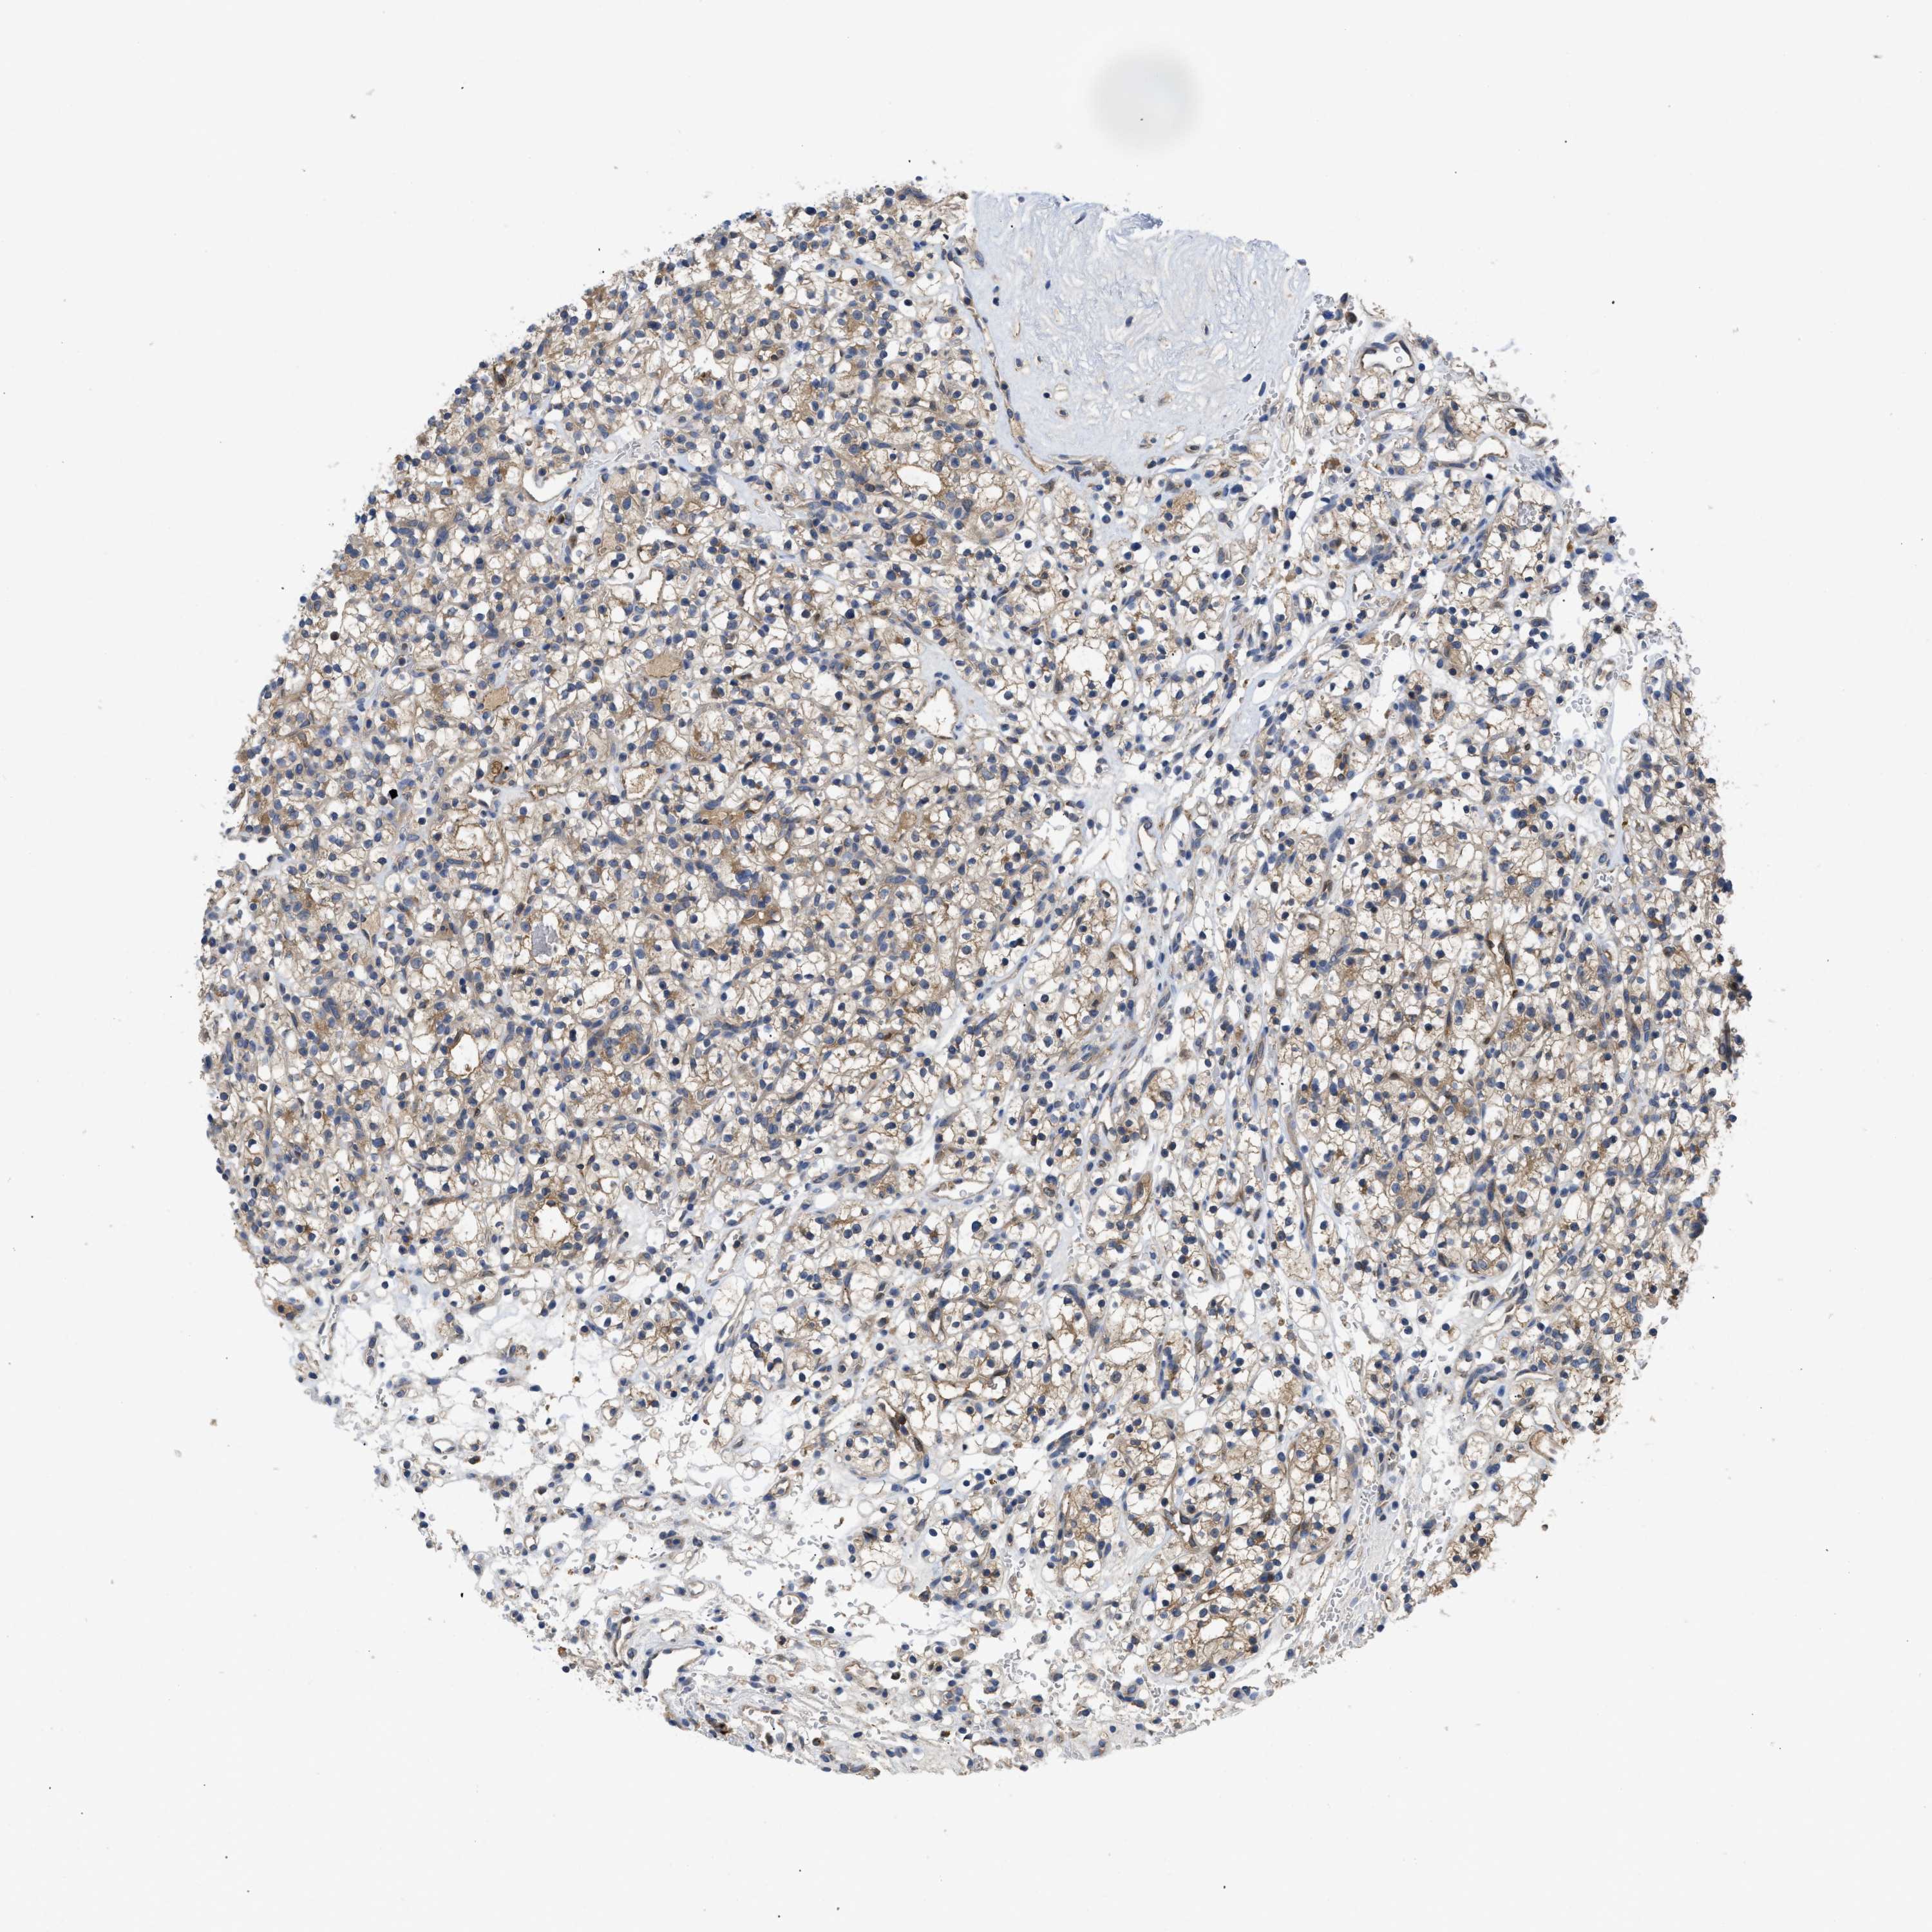

KIDNEY RENAL PAPILLARY CELL CARCINOMA (TCGA) - Interactive survival scatter ploti

The Survival Scatter plot shows the clinical status (i.e. dead or alive) for all individuals in the patient cohort, based on the same data that underlies the corresponding Kaplan-Meier plots. Patients that are alive at last time for follow-up are shown in blue and patients who have died during the study are shown in red.

The x-axis shows the expression levels (FPKM) of the investigated gene in the tumor tissue at the time of diagnosis. The y-axis shows the follow-up time after diagnosis (years). Both axes are complimented with kernel density curves demonstrating the data density over the axes. The top density plot shows the expression levels (FPKM) distribution among dead (red) and alive patients (blue). The right density plot shows the data density of the survived years of dead patients with high and low expression levels respectively, stratified using the cutoff indicated by the vertical dashed line through the Survival Scatter plot. This cutoff is automatically defined based on the FPKM cutoff that minimizes the p-score. The cutoff can be changed by dragging the vertical line or by entering a cutoff value in the square labeled "Current cut-off".

Under the Survival Scatter plot the p-score landscape (black curve; left axis) is shown together with dead median separation (red curve; right axis). Dead median separation is the difference in median mRNA expression between patients who have died with high and low expression, respectively. It is calculated as follows: median FPKM expression of dead patients with high expression - median FPKM expression of dead patients with low expression. This is intended to aid the user in visually exploring custom cutoffs and the associated p-scores and dead median separation.

Individual patient data is displayed and can be filtered by clicking on one or more of the category buttons on the top of the page. Categories describing expression level and patient information include: high, low, alive, dead, female, male and tumor stages. The scale of the x-axis can be toggled between linear and log-scale by clicking on the "x log" button. Mouse-over function shows TCGA ID, patient information and mRNA expression (FPKM) for each patient.

& Survival analysisi

Kaplan-Meier plots summarize results from analysis of correlation between mRNA expression level and patient survival. Patients were divided based on level of expression into one of the two groups "low" (under cut off) or "high" (over cut off). X-axis shows time for survival (years) and y-axis shows the probability of survival, where 1.0 corresponds to 100 percent.

RNF216 is not prognostic in Kidney Renal Papillary Cell Carcinoma (TCGA)

Best expression cut offi

Based on the FPKM value of each gene, patients were classified into two groups and association between prognosis (survival) and gene expression (FPKM) was examined. The best expression cut-off refers the FPKM value that yields maximal difference with regard to survival between the two groups at the lowest log-rank P-value. Best expression cut-off was selected based on survival analysis .

When clicking on this number, the vertical dashed line indicating cut-off, the interactive survival plot, and the Kaplan-Meier curve will be adjusted to show results based on the best expression cut-off.

: 16.15